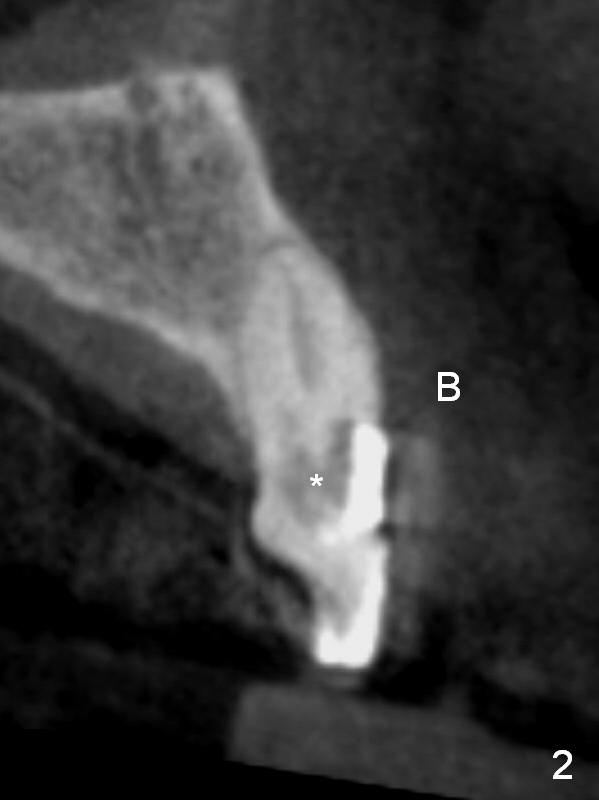

A 70-year-old man (CK) has history of several tooth fracture after RCT. When the tooth #10 develops pulpitis (Fig.1 CBCT sagittal section), he is reluctant to accept RCT. With several upper right and upper left implant placement, the affected tooth may not be so vulnerable to fracture. RCT will be tried first. If the caries proves to be too extensive (Fig.2 (coronal section) *), the tooth will be extracted with socket shield technique. Effort will be exerted for complete apex removal, followed by Metronidazole socket treatment. A 3.8x13 mm UF implant is placed; an angulated or gold coated abutment may be required (Fig.3). Bone density is 500-600 HU.